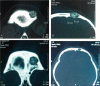

Primary intraosseous cavernous hemangiomas (PICHs) are benign vascular tumors that may involve any part of the body. PICH occurs more frequently in the spine and less commonly in skull. The earliest description in the English literature was in 1845 by Toynbee, who reported a vascular tumor arising in the confines of the parietal bone. Skull PICHs do not always have typical radiologic features and should always be considered in the differential diagnosis of malignant skull lesions. We now reviewed and analyzed related literatures in detail with reporting a rare case of PICH in the left front bone that was surgically resected.